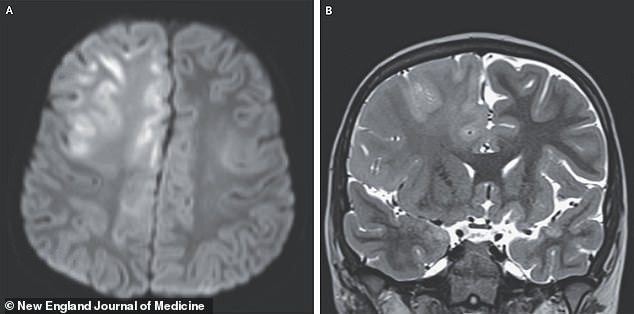

The disease, which spreads easily through coughs and sneezes, begins with symptoms like fever, cough, and a telltale rash that spreads across the body. But for some, the danger doesn't end there. In a recent case study published in the New England Journal of Medicine, doctors described a seven-year-old boy who had been infected with measles at just seven months old in Afghanistan. Though the initial infection seemed to pass without major complications, the child later developed seizures, cognitive decline, and spasming reflexes that left him unable to speak. An MRI revealed severe brain damage, leading to a diagnosis of SSPE, a condition with a 95% mortality rate.

SSPE, once considered a medical rarity, is making a troubling comeback. While the U.S. typically sees only four to five cases annually, the latest data shows a sharp increase. The disease progresses slowly, causing the brain to deteriorate over months or years. Most patients survive about four years after symptoms begin, though some may live as long as 12 years before succumbing. The boy in the case study died a year after his symptoms started, a grim reminder of the disease's relentless progression.